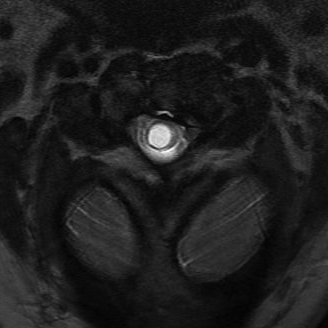

MRI

Most sensitive investigation

- main differential is oedema

- need T1 image

Look for obstructions

- ACM

- spinal cord tumours